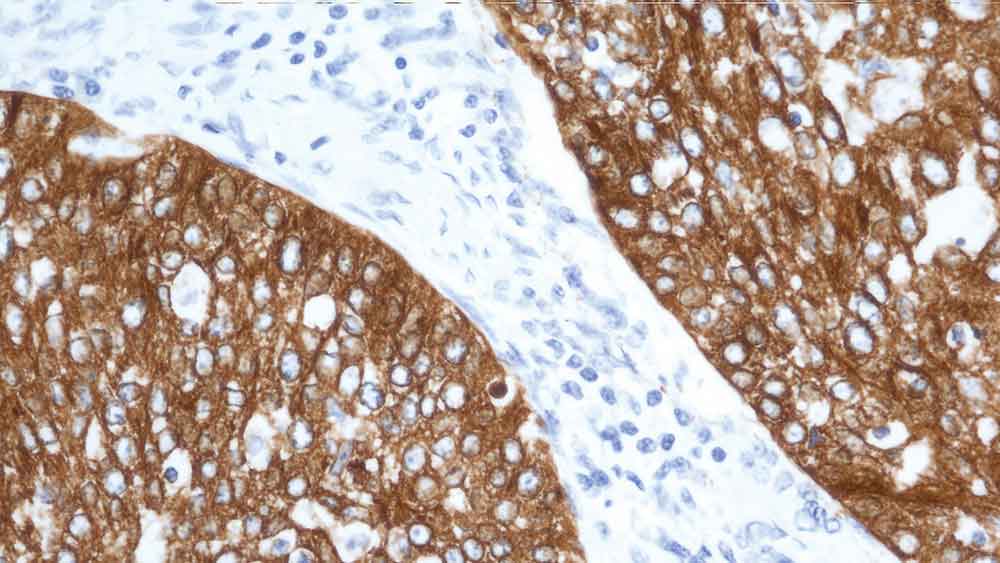

Human breast cancer: immunohistochemical staining for Epithelial Membrane Antigen. Note membrane staining of neoplastic cells. Epithelial Membrane Antigen: clone GP1.4

Epithelial Membrane Antigen (EMA), also known as episialin, is reported to be expressed in a variety of normal and neoplastic epithelia. It has been reported that markers to CD45 (LCA) when used in conjunction with markers to EMA are useful in labeling cells of lymphoid origin, whereas the combination of anti-cytokeratin antibodies together with EMA is useful to characterize cells of epithelial origin. EMA is also notably described to be expressed in a subset of Hodgkin's lymphomas.